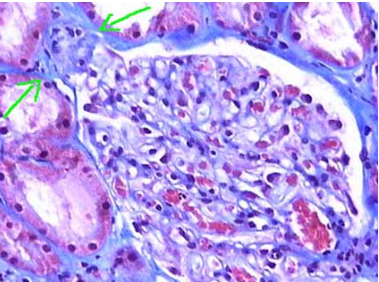

A

Asas de alambre

* Lupus Clase 4 proliferativa difusa >50% asas